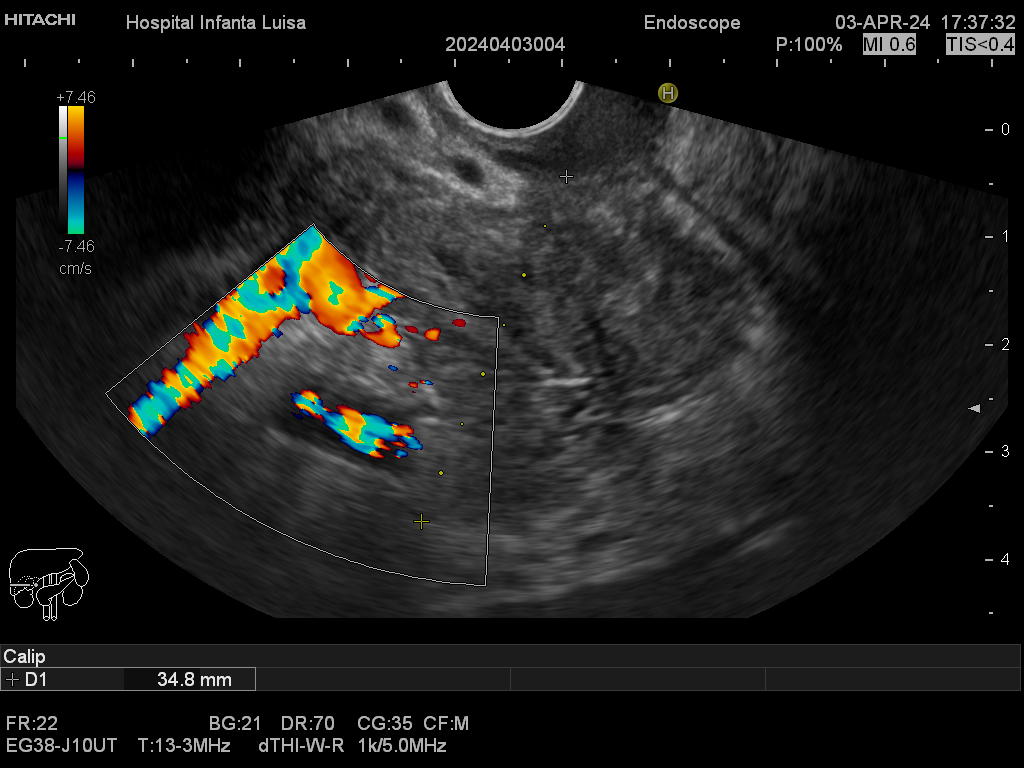

La Ecoendoscopia o Ultrasonografía endoscópica (USE) consiste en la exploración del tracto digestivo superior (principalmente), o de los últimos centímetros del tracto digestivo inferior (recto, generalmente), con un tipo de endoscopio especial que se llama ecoendoscopio.

La Ecoendoscopia, como su nombre indica, combina dos tipos de técnicas: la endoscopia y la ecografía, pues nos aporta simultáneamente una visión endoscópica (similar, aunque no igual, a la alcanzada con el gastroscopio y el colonoscopio) y ecográfica, que permite la visualización y estudio de las estructuras que quedan por fuera y están en contacto con la pared del esófago, estómago, duodeno o colon.

Mediante dicha exploración se explora minuciosamente los tramos mencionados, permitiendo valorar distintas patologías como lesiones propias de la pared de estos órganos (determinado su profundidad y extensión), o lesiones que quedan en órganos anexos, pero por fuera, de ahí la importancia de la visualización ecográfica, como páncreas, mediastino, hígado, diferentes adenopatías o masas indeterminadas previamente, entre otros.

Igualmente, es una técnica básica hoy día en el estudio de todo tipo de lesiones pancreáticas, en la determinación de formaciones subepiteliales esofágicas, gástricas (más frecuentes) o duodenales, o en el estadiaje de patología tumoral a estos niveles. La Ecoendoscopia permite la toma de biopsias a estos niveles, con control endoscópico y ecográfico, siendo una técnica de gran rentabilidad diagnóstica y seguridad.